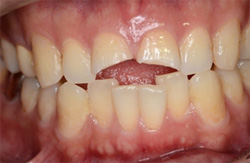

先週、救急で歯冠の破折の患者さんがいらしました。当日の朝転倒し、前歯2本が大きく折れてしまったそうです。

前歯2本が大きく折れてしまってます。 |

神経も大きく露出しています。 |